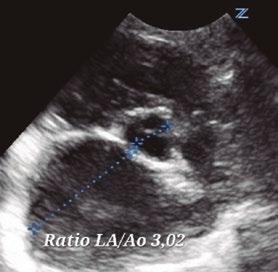

Utilidad de la ecografía cardiaca y pulmonar en urgencias

Utilidad clínica de la ecografía pulmonar y cardiaca en urgencias